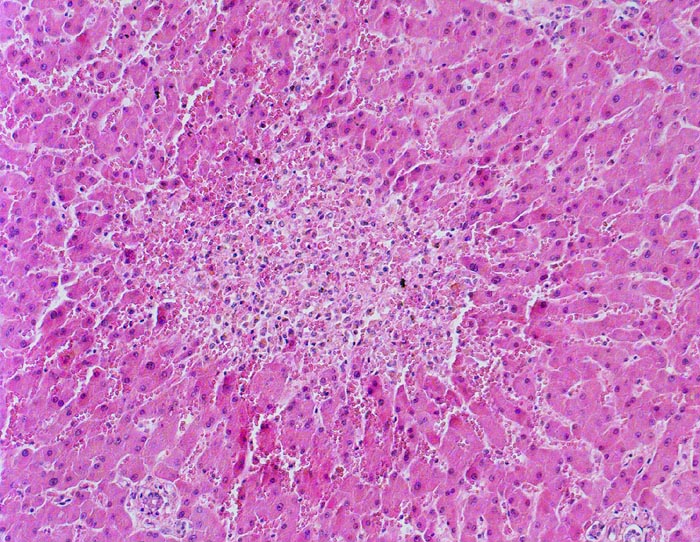

PathoPic – image database / PathoPic ID 3249 - Zonale perizentrale Parenchymnekrose bei Schock

Zonale perizentrale Parenchymnekrose bei Schock

vaskulär / Durchblutungsstörung

Leber

Im Bildzentrum die Zone 3. Ein Zentralvenenlumen ist nicht erkennbar. Anstelle von regelrecht aufgebautem Parenchym ist eine blutdurchtränkte Zone mit Entzündungszellen anstelle von Hepatozyten getreten. Die Sinusoide der Zone 2 zeigen eine Blutstase.

Schweres akutes Rechtsherzversagen bei multiplen zentralen und perizentralen Lungenembolien.

Histologie

100